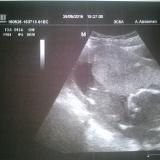

sono di 6settimane precise 😍….e ho visto l’embrioncino sembrava una stellina…